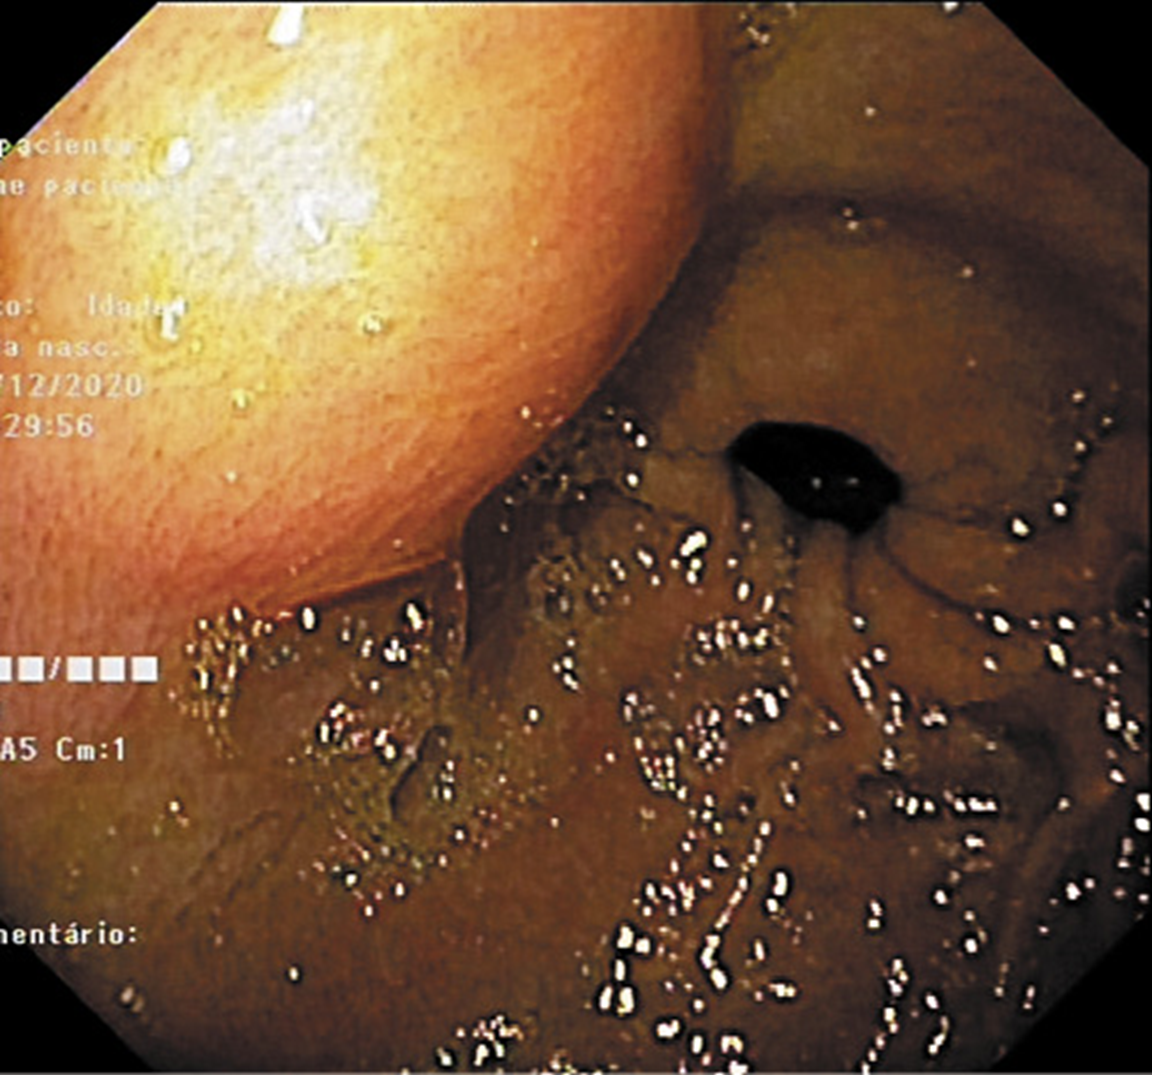

A 37-year-old leucodermic woman with no relevant past history presented with 1-month history of new-onset epigastric pain and bloating. She denied any other symptoms. She underwent an esophagogastroduodenoscopy that revealed a 25-mm subepithelial lesion in the gastric antrum (Fig. 1). Tunnel biopsies were done and were unrevealing. She underwent an endoscopic ultrasound (EUS) that showed a 25-mm hypoechogenic subepithelial lesion originating in the muscularis propria (Fig. 2). EUS-guided fine-needle aspiration (FNA) with a 25-G needle (Boston Scientific®) was performed (2× passes using suction technique), revealing cell nests without atypia, that were focally positive for smooth-muscle actin and synaptophysin, and negative for chromogranin and CD117. KIT and PDGFRA mutations were also negative. Unfortunately, the sample was inadequate for further study. A staging CT was performed excluding distant metastasis. Since investigations thus far were inadequate to exclude a malignant process, she underwent laparoscopic-wedge gastrectomy. Histopathology revealed a solid, epithelioid, and richly vascular tumor without cellular atypia (Fig. 3). Immunohistochemistry was similar to that previously performed and complemented with positive calponin (Fig. 4) and negative cytokeratin AE1/AE3 (Fig. 5), making the diagnosis of a glomus tumor.

Fig. 1: Esophagogastroduodenoscopy revealed a 25-mm subepithelial gastric lesion in the gastric antrum.